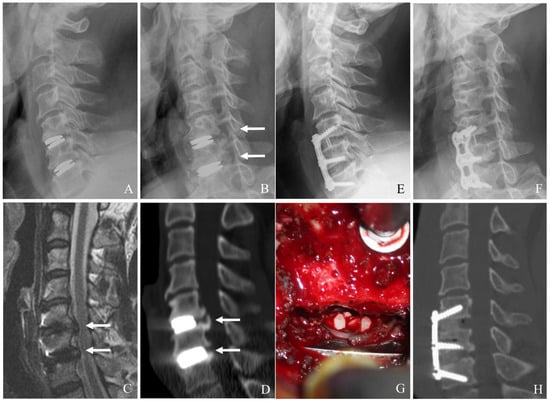

Redoing CDA at the adjacent level is a motion-preserving option for carefully selected patients. It aims to maintain cervical mobility and reduce the long-term risk of adjacent segment degeneration (Figure 5) [27,28,29].

6.5. Laminoplasty for ASD After CDA

Laminoplasty is a motion-preserving posterior decompression technique particularly useful for multilevel cervical stenosis without significant instability. It expands the spinal canal while maintaining the integrity of posterior elements (Figure 6A–H) [22,23,24,25,26]. Key indications include the following:

Figure 5. Plain X-rays (A), magnetic resonance image (B,C) showing kyphosis of C5–6 prosthesis and C6–7 adjacent segment disease with left foraminal stenosis and disc herniation (white arrows). The patient underwent removal of C6–7 redo cervical disc arthroplasty (D).

Figure 6. Plain X-rays (A), magnetic resonance image (B,C), computed tomography (D), and clinical photo (G) showing hypertrophy of ligamentum flavum at C4–6 and facet cyst at C4–5 causing cord compression (white arrows). The patient underwent C4accept–6 open-door laminoplasty and removal of facet cyst, leading to complete cord decompression (E,F,H).